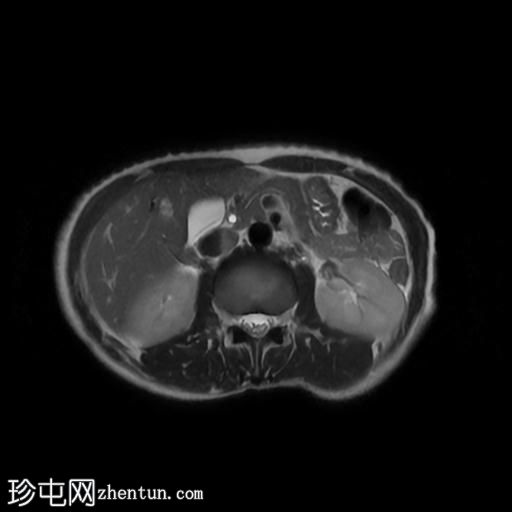

轴位

T2加权像

该宫颈癌体积较大,局部晚期,大小为22 x 40 x 42 mm,起源于宫颈左后外侧壁,向下延伸至阴道上三分之一处,位于宫颈中后外侧壁。

病变还累及左侧前外侧的宫旁组织。

左侧髂内静脉分叉下方可见一异常信号淋巴结肿大,最大短轴直径(SAD)为 8 mm。该淋巴结在弥散加权成像(DWI)上显示水限制,并有对比增强。

影像学检查结果提示,根据 FIGO 分期系统,该患者为宫颈癌 IIIC1 期。